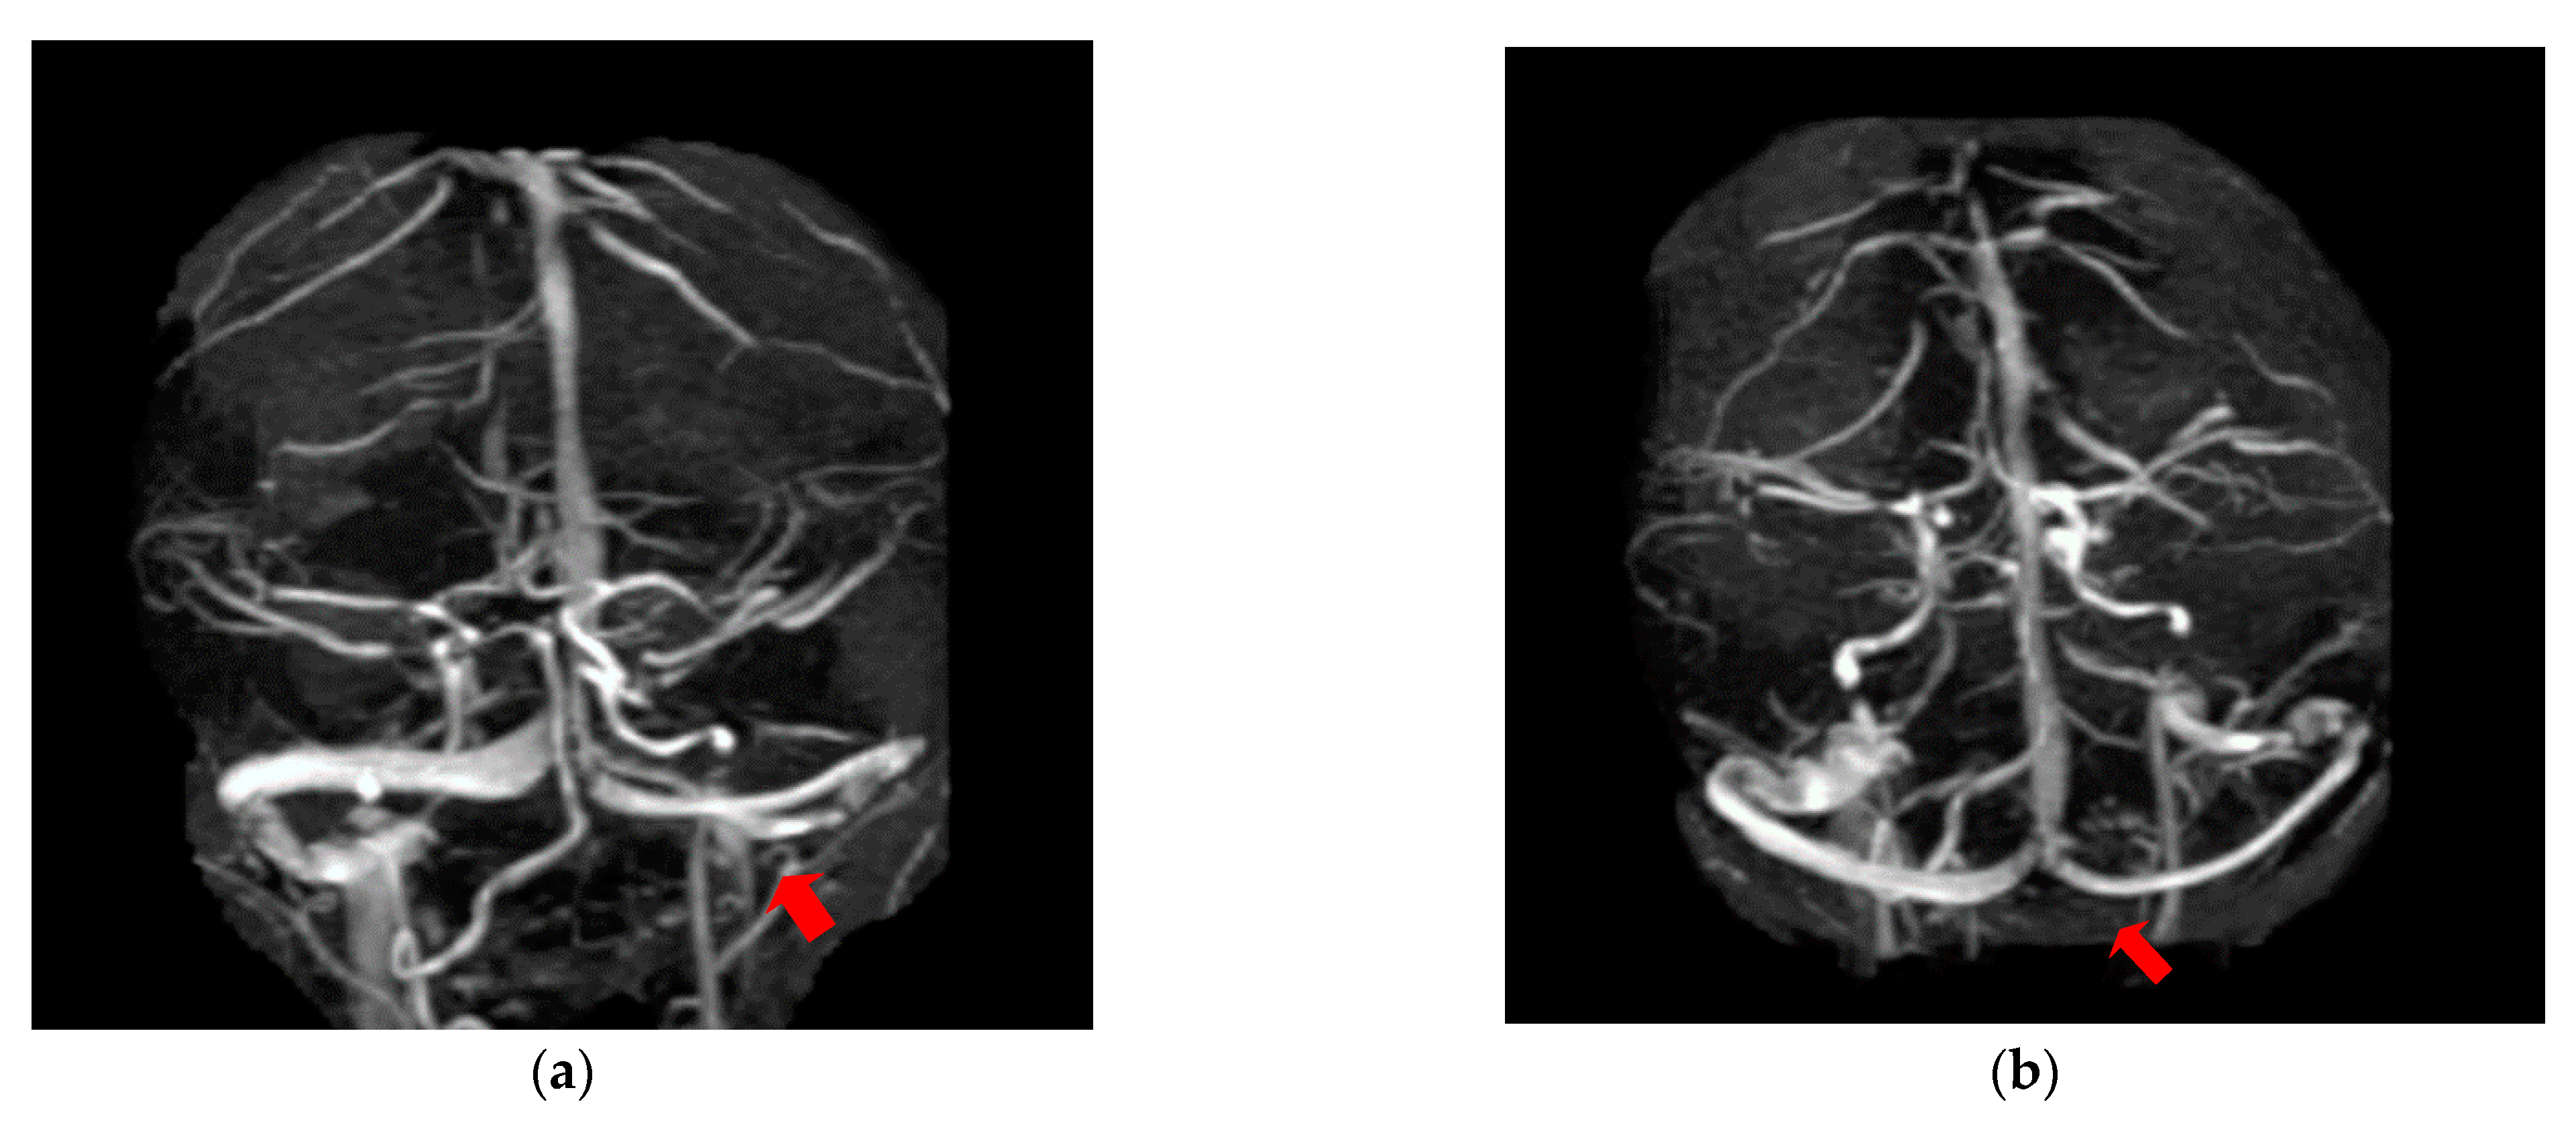

The second case was a female, 31 years old, with an etiology of thrombophlebitis accentuated by the presence of the MTHFR C677T gene polymorphism- homozygous phenotype. The patient was hospitalized with superficial coma, generalized seizures and left hemiparesis. In the course of evolution, subsequent to the cerebral post thrombotic syndrome and edematous encephalopathy, the patient presented symptomatology characterized by generalized seizures under anticonvulsivant treatment and also psychical disturbances (irritability, aggressiveness). The patient was clinically and neuroimagistic assessed after six month and six years from the onset of the disease. The image features can be seen in Figure 3, Figure 4 and Figure 5.

Figure 5. MR- venography 2D- TOF (time of flight) in the coronal plane reveals the permeabilization of the superior sagittal sinus but in the right lateral sinus persist the absence of the flow after six years from the onset of the disease.